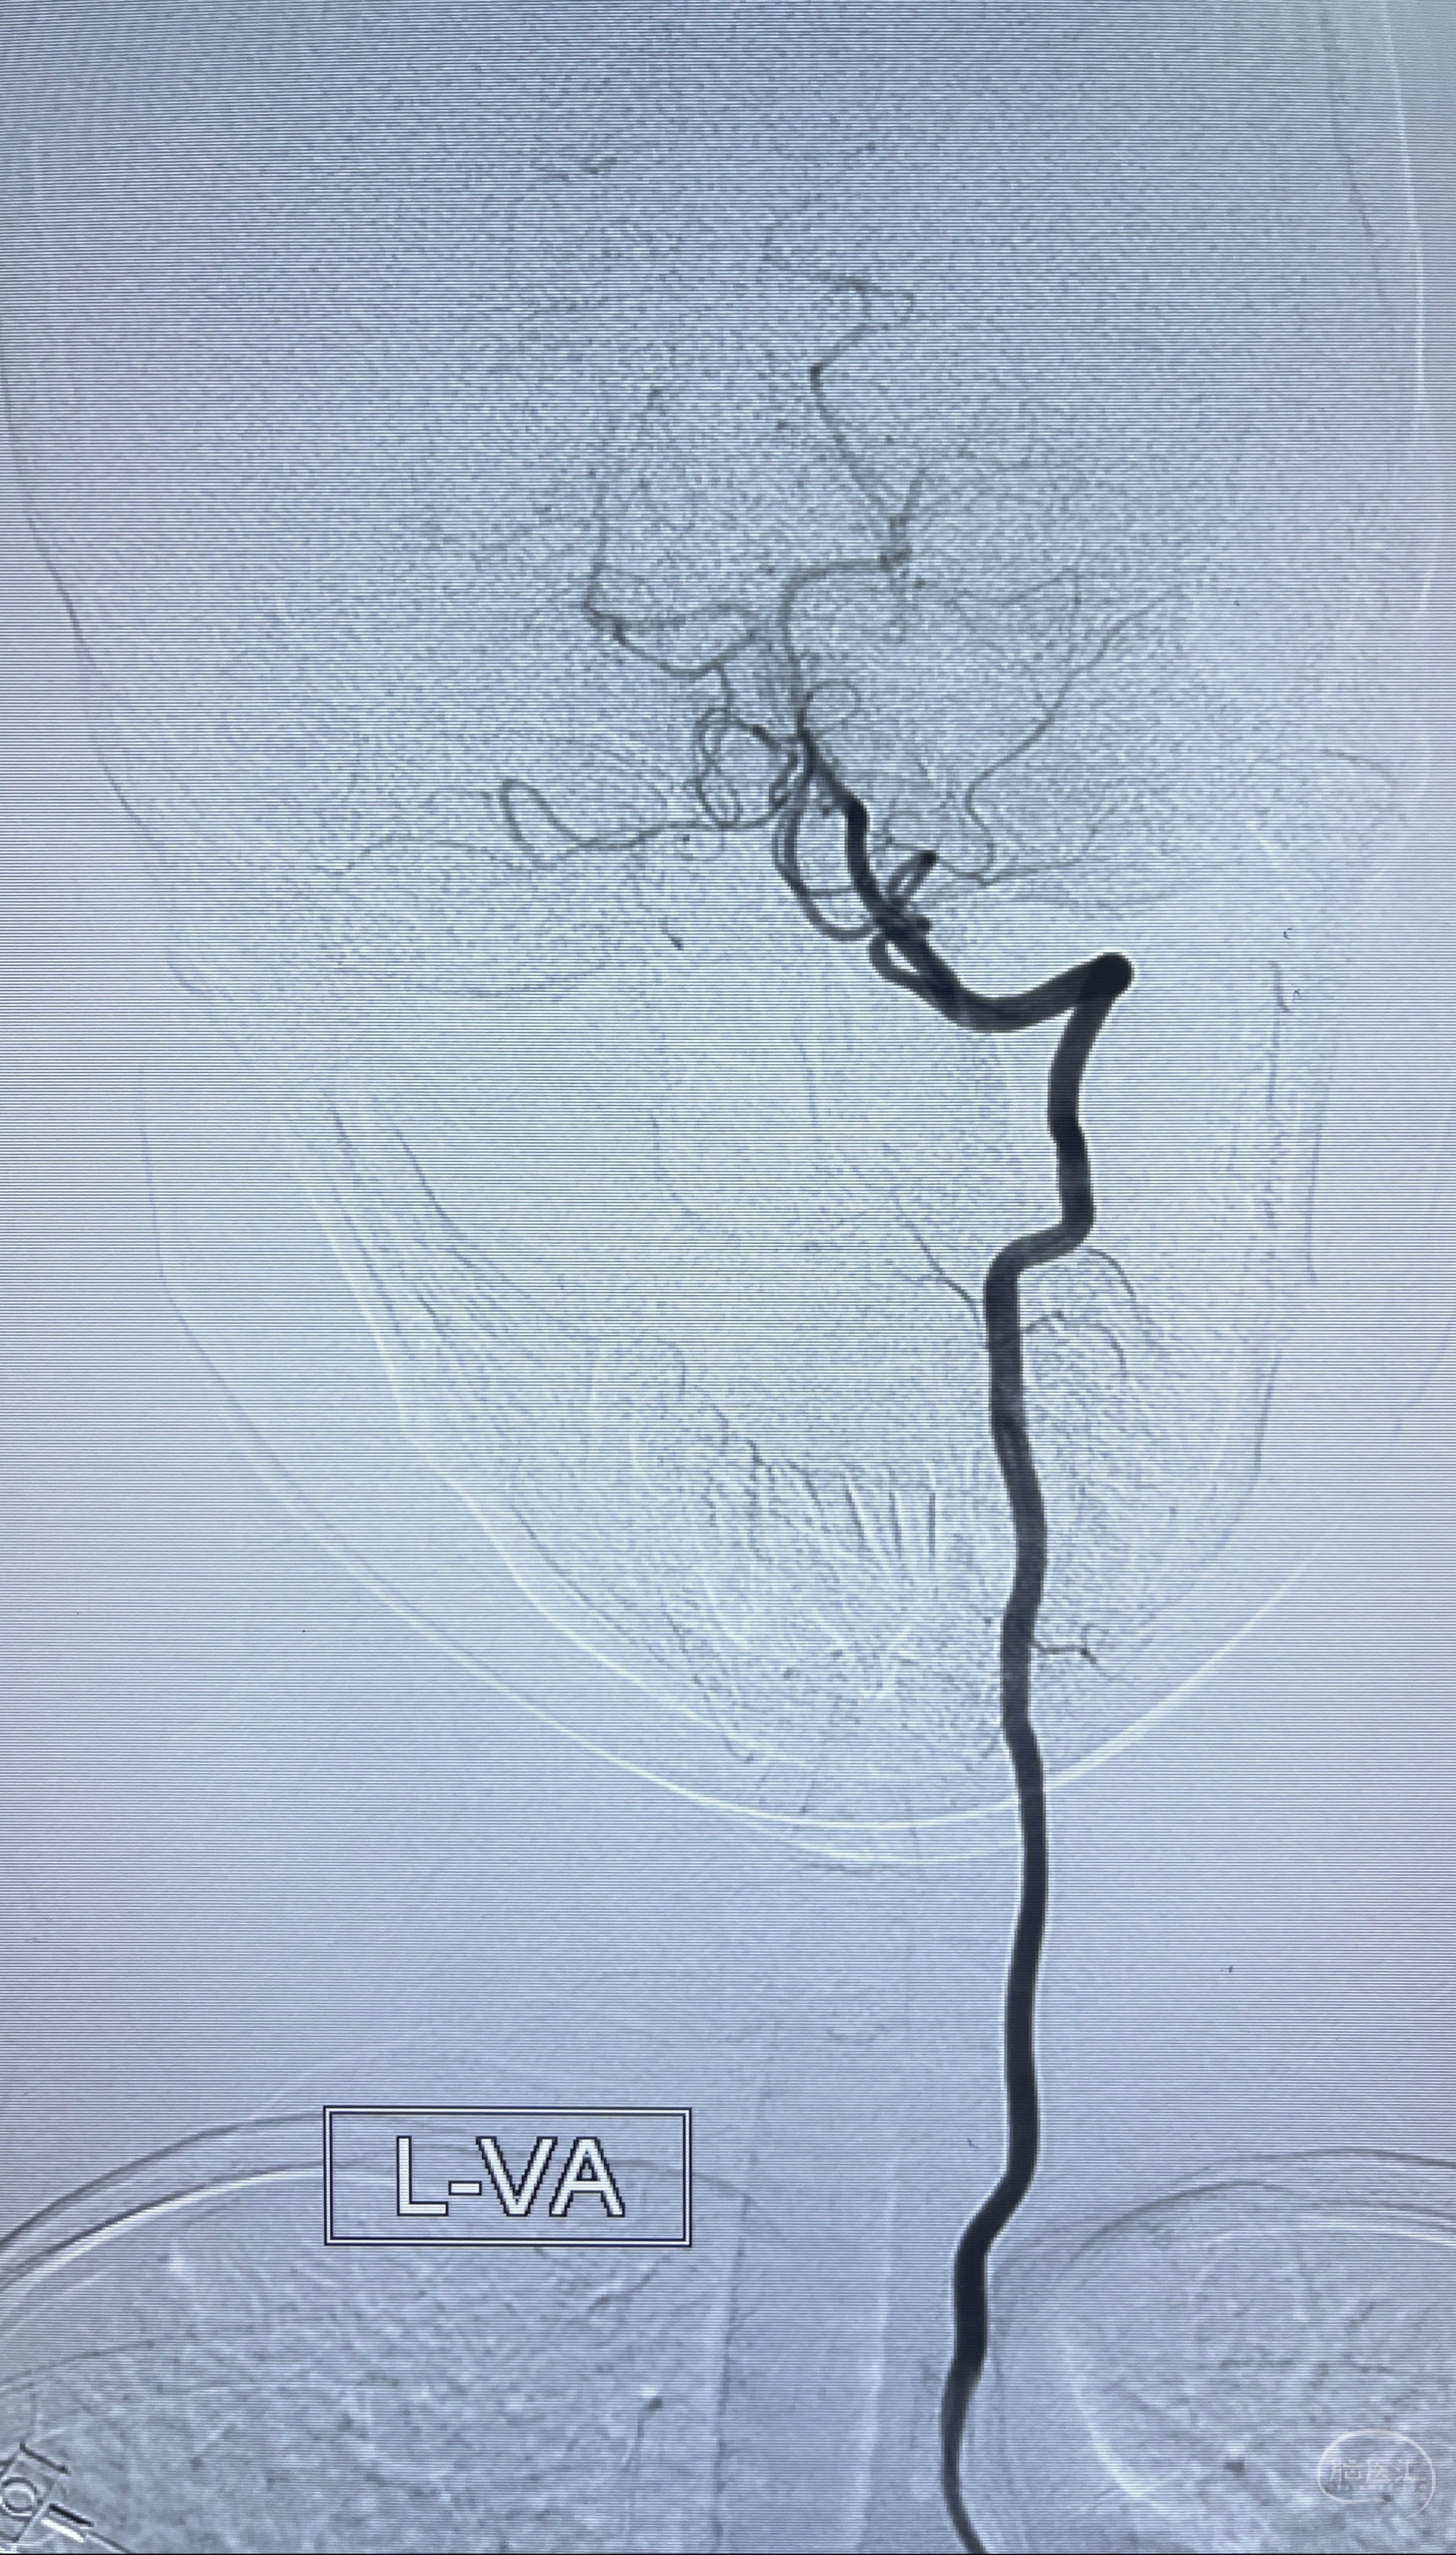

2023-08-14DSA:

左侧大脑中动脉动脉瘤,约2.6-2.8-3.4-2mm大小(瘤颈部、瘤体部、瘤高)